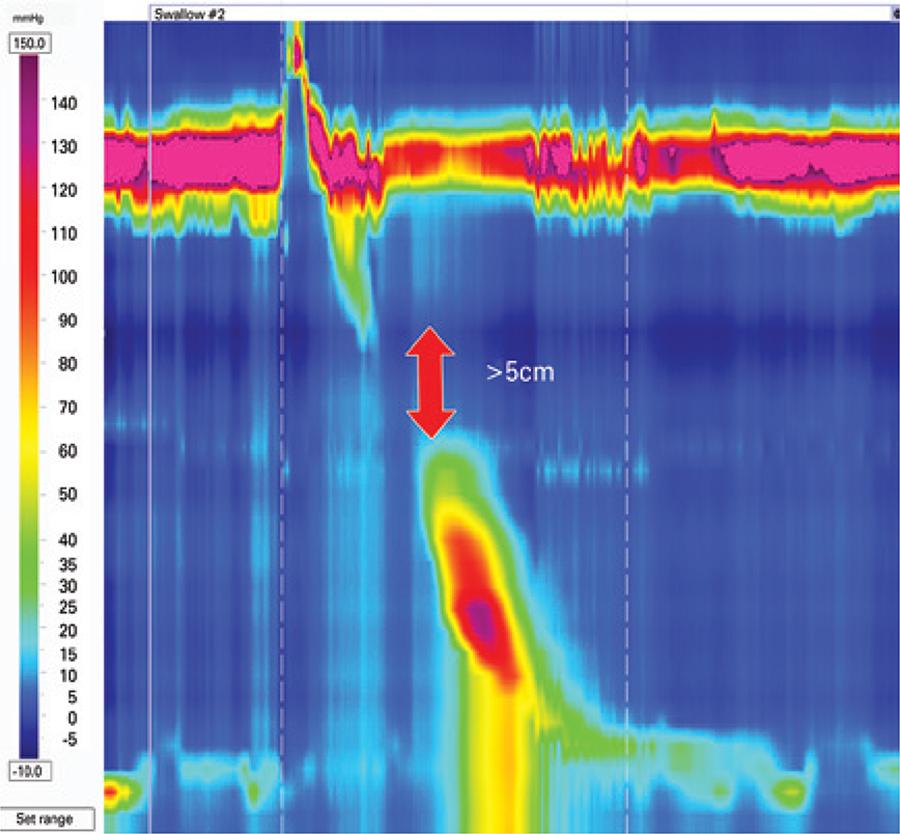

High resolution manometry changed several esophageal motility paradigms. The 3.0 Chicago Classification defined manometric criteria for named esophageal motility disorders. We present a pictorial atlas of motility disorders. Achalasia types, esophagogastric junction obstruction, absent contractility, distal esophageal spasm, hypercontractile esophagus (jackhammer), ineffective esophageal motility, and fragmented peristalsis are depicted with high-resolution manometry plots.